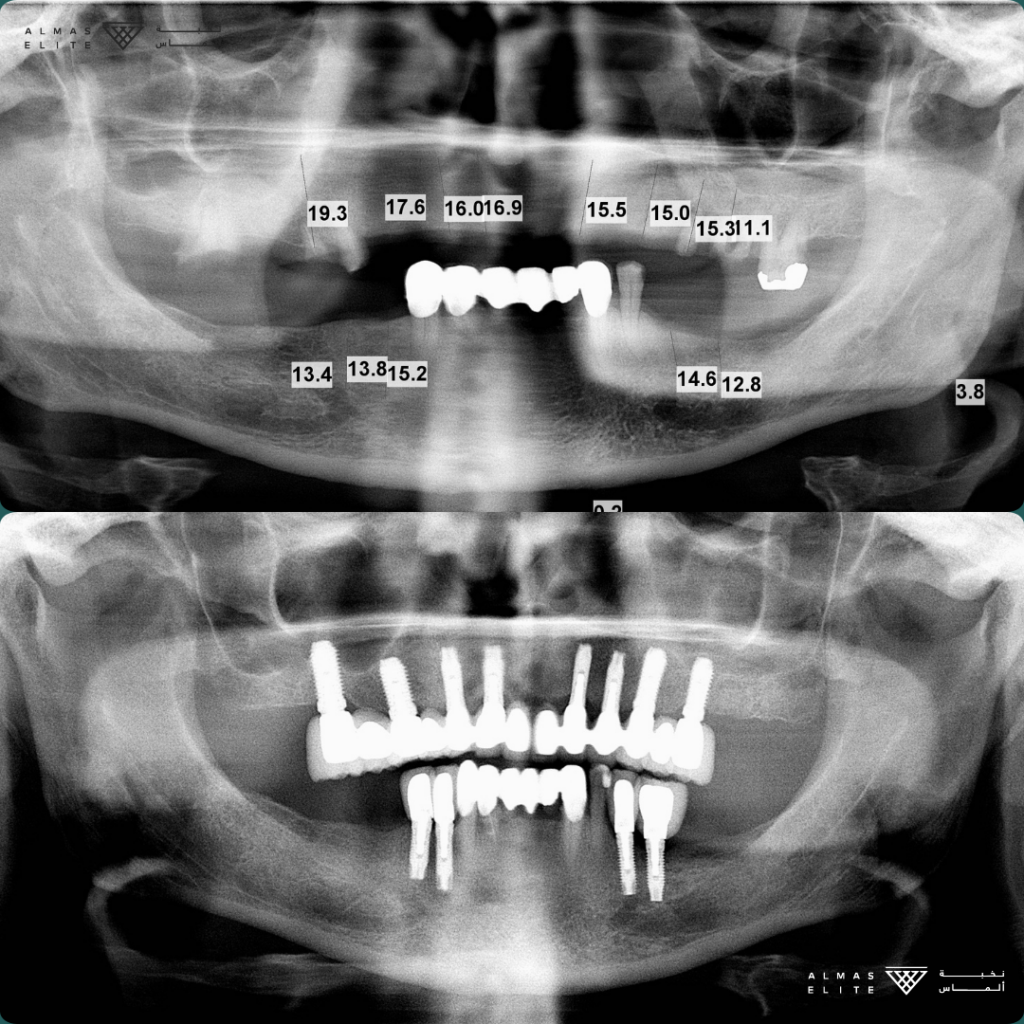

القرار النهائي لملاءمة الزراعة يتم بعد استشارة الطبيب، والفحص السريري، والتصوير الإشعاعي (مثل الأشعة ثلاثية الأبعاد) حسب الحاجة.

• الفحص الكامل: يشمل الأشعة ثلاثية الأبعاد وتحليل جودة وكثافة العظم.

٢) خلع السن (إن وجد)

يُفضّل خلع السن التالف أولاً، وقد تُجرى الزراعة مباشرة في نفس الجلسة

(الزراعة الفورية) إذا كانت الحالة مناسبة، من حيث كثافة العظم وعدم وجود عدوى نشطة.

٣) المرحلة الجراحية (Stage 1)

• الزراعة التقليدية: بعد شفاء موضع الخلع بـ 6–8 أسابيع في كثير من الحالات.

• الزراعة الفورية: تتم بعد الخلع مباشرة بشرط توفر المعايير اللازمة.

تليها فترة اندماج عظمي تستغرق من 3 إلى 6 أشهر حسب الحالة الصحية وجودة العظم.

٤) المرحلة التركيبية (Stage 2)

• فتح اللثة وتركيب Healing Abutment فوق الزرعة.

• أخذ المقاسات أو إجراء المسح الرقمي للأسنان.

• تركيب التاج النهائي في العادة خلال أسبوعين تقريبًا من أخذ المقاسات.